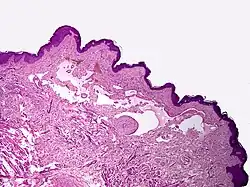

Cavernous lymphangioma, H&E stain. Irregular, dilated spaces are visible in dermis.

Lymphangiomas have traditionally been classified into three subtypes: capillary and cavernous lymphangiomas and cystic hygroma. This classification is based on their microscopic characteristics. A fourth subtype, the hemangiolymphangioma is also recognized.[12]

Cavernous lymphangiomas

Composed of dilated lymphatic channels, cavernous lymphangiomas characteristically invade surrounding tissues.

Microscopically, the vesicles in lymphangioma circumscriptum are greatly dilated lymph channels that cause the papillary dermis to expand. They may be associated with acanthosis and hyperkeratosis. There are many channels in the upper dermis which often extend to the subcutis (the deeper layer of the dermis, containing mostly fat and connective tissue). The deeper vessels have large calibers with thick walls which contain smooth muscle. The lumen is filled with lymphatic fluid, but often contains red blood cells, lymphocytes, macrophages, and neutrophils. The channels are lined with flat endothelial cells. The interstitium has many lymphoid cells and shows evidence of fibroplasia (the formation of fibrous tissue). Nodules (A small mass of tissue or aggregation of cells) in cavernous lymphangioma are large, irregular channels in the reticular dermis and subcutaneous tissue that are lined by a single layer of endothelial cells. Also an incomplete layer of smooth muscle also lines the walls of these channels. The stroma consists of loose connective tissue with a lot of inflammatory cells. These tumors usually penetrate muscle. Cystic hygroma is indistinguishable from cavernous lymphangiomas on histology.[7]